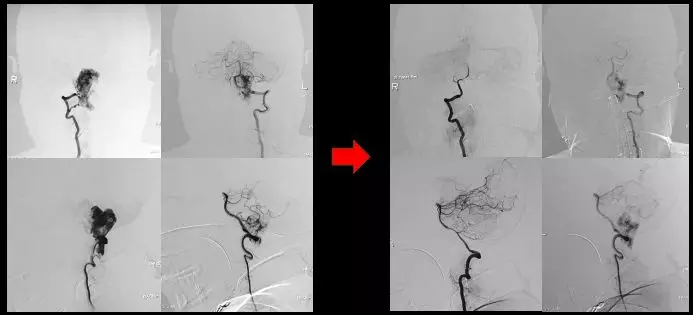

术中DSA

术中栓塞前后结果比较